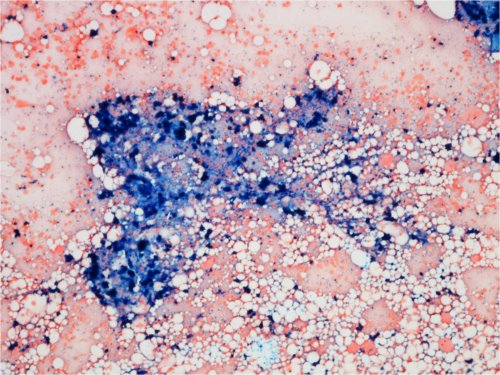

Luuytimen rautavärjäys

• Lapsen normaalissa luuytimessä on yleensä hyvin vähän kudosrautaa, ja rautavärjäys on negatiivinen.

• Kudosrauta on lisääntynyt ja siis rautaa nähtävissä luuytimen rautavärjäyksessä tiloissa, joissa kehittyy esim. transfuusiosideroosi.

• Kudosrautaa on nähtävissä luuydinbiopsiassa sekä stroomassa tippavärjäyslasin keskiosassa.

Kuva 35. Luuytimen rautavärjäys. Potilaalla beetatalassemia major ja transfuusiosideroosi.

Kuva 36. Luuytimen rautavärjäys. Rauta (sininen väri) kerääntyy makrofageihin. Beetatalassemia major ja transfuusiosideroosi.